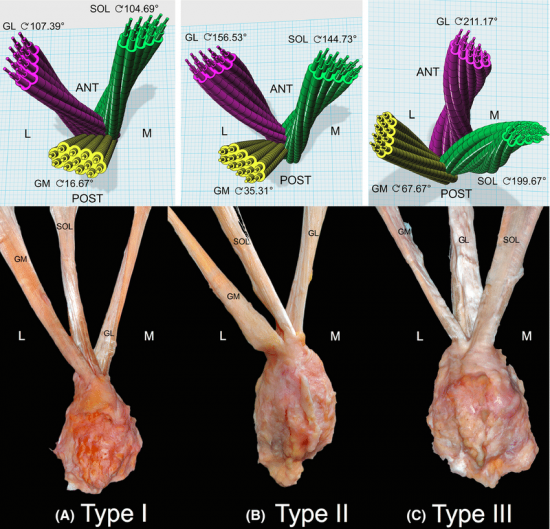

The Twisted Structure of the Achilles Tendon